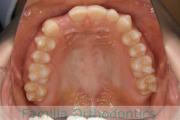

No.21V-424

- 主な症状:

- 上顎前突

- その他の症状:

- 叢生

- 年齢:

- 23歳

- 性別:

- 女性

- 抜歯部位

- 上:

- 44

- 下:

- 8|2

- 主な使用装置:

- FEA 022

- 治療にかかった費用:

- 90万円

でこぼこと八重歯が気になるとのことで来院されました。上下のあごのズレ(下顎の後退)が相当に強かったため、下は左右から小臼歯を抜歯する代わりに下の前歯を一本だけ抜歯する治療方針を採用させていただきました。

下顎の後退は呼吸機能にも影響しますので、ある一定上のズレがある方は、下あごの前方移動術のオペも検討します。こちらの方は、そこまでリスクが高いとは判断しませんでした。